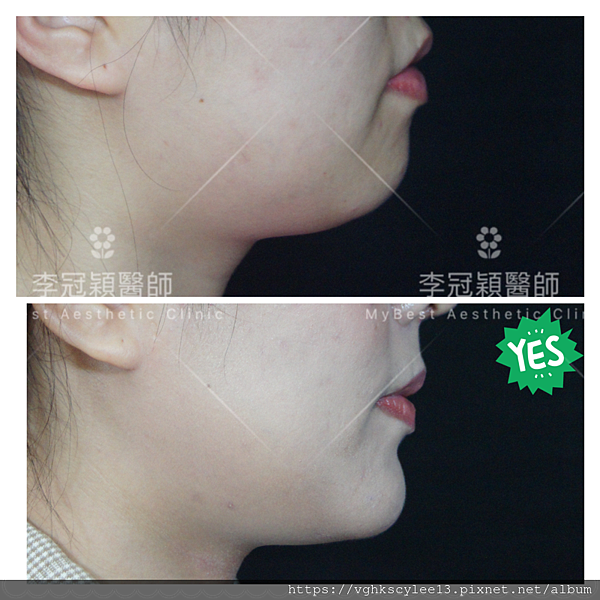

下圖案例:下巴整形打造V型臉的效果(客製化goretex複合式假體)

下圖:後縮小下巴會堆積雙下巴和嘴邊肉皮膚,視覺老態。經過客製化3D導航下巴改善外觀老態,提升年輕化。

過短後縮下巴,因組織支撐力弱而容易有雙下巴(上圖),嘴邊肉(下圖)以及下顎腺不明顯,整體而言除了失衡還有點流失下垂的『老態』。

案例:下巴整形(客製化goetex下巴假體)

下圖: 3D客製化精準墊下巴(goretex)

案例分享:3D列印導航客製化goretex下巴